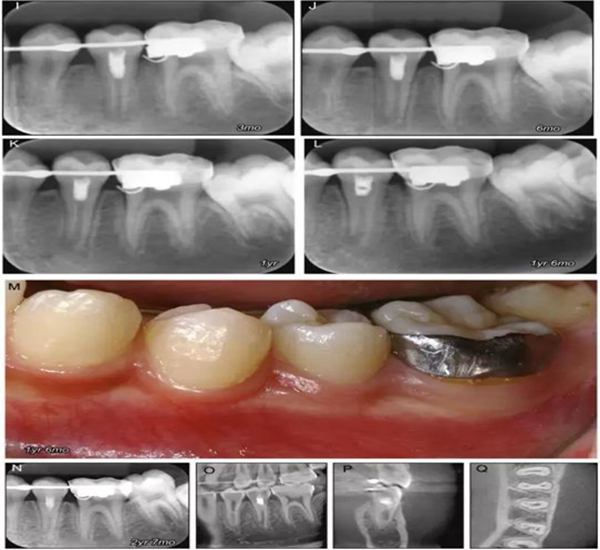

原則上年輕恒牙的牙髓治療應(yīng)盡可能以保存活髓的方式以便不影響牙根繼續(xù)發(fā)育。本文3個(gè)病例均描述了根尖尚未發(fā)育完成的下頜前磨牙被確診為牙髓壞死伴有大面積根尖病損,治療過程中在根管內(nèi)發(fā)現(xiàn)了部分活髓,而采用活髓切斷后都取得了很好的療效。